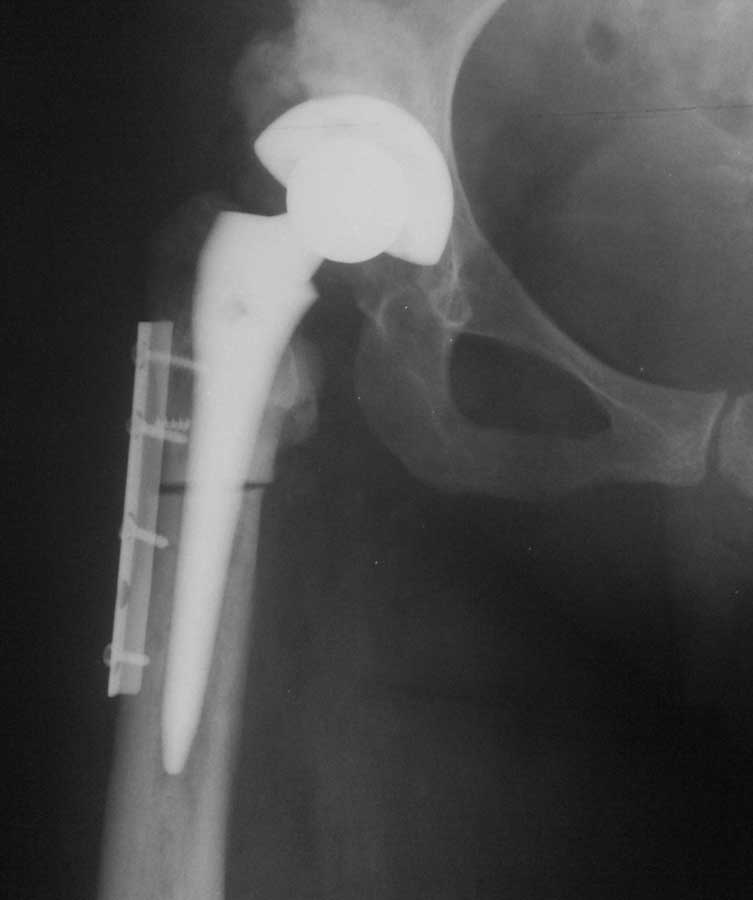

Уважаемые коллеги, к нам поступила женщина 45 лет с такой вот ситуацией: Операция около 1,5 месяцев назад: тотальное б/ц эндопротезирование с остеотомией проксимального отдела бедра. Послеоперационный период - без особенностей, рана зажила первично, выписана домой. В анамнезе в детском и юношеском возрасте несколько оперативных вмешательств на вертлужной впадине и бедре по поводу врожденного вывиха бедра, судя по рубцам, протекавшие не совсем гладко. около 2,5 недель назад пациентка начала отмечать вечерние подъемы температуры до 38. примерно в это же время выявлен высокий тромбоз поверхностной бедренной и общей бедренной вен, несмотря на прием антикоагулянтов. Пунктирован сустав - получен рост золотистого стафилококка. Учитывая острый тромбоз, назначена супрессивная а/б терапия с учетом чувствительности. В настоящее время: тромбоз с положительной динамикой с признаками реканализации, небольшой лейкоцитоз, СРБ до 12, вечерние свечки до 38 (не каждый день), субъективно - чувствует себя лучше. Локально: плотный отек в области п/о рубца, гиперэмия, небольшое количество пузырей с серозным отделяемым (сожалею, сегодня не успел сфотографировать). Вопросы: -какова вероятность локализации процесса в мягких тканях или не стоит выдавать желаемое за действительное? - объем ревизионного вмешательства: сохранять эндопротез или нет? одноэтапно или двухэтапно? На фоне остеотомии бедра испльзовать цементный спейсер или поробовать импакционную пластику с добавлением антибиотика или пластику - дистально, цемент проксимально?

1. Если материал получен из сустава, и конец иглы "нащупывал" компоненты протеза или кость - это перипротезная инфекция.

2. Бедренный компонент не выглядит стабильным, и стабильным на протезе с прокимальной фиксацией быть не может. Антиротационная пластинка слегка удерживает дистальный отломок, а плоскость остеотомии сложно назвать хорошо адаптированной. Из чего следует - бедренный компонент удалять. Вертлужный, если стабилен, можно оставить с заменой вкладыша

3. Вопрос о тактике сложный. На сегодня преимуществ одно или двухэтапной ревизии не выявлено. Вопрос решается индивидуально в каждом конкретном случае. Убирая бедренный компонент, кроме борьбы с инфекцией, нужно стабилизировать бедро. Следовательно нужна нога с дистальной фиксацией - типа ревизионной Вагнера. Ресурсы позволят?

4. Костная импакционная пластика используется при значитальном дефиците костного ложа, которого здесь вроде не наблюдается. Поэтому если речь пойдет о спейсере, то я за цементный без пластики.

2.а какие признаки нестабильности его есть? Явной нестабильности точно нет, вероятной - под большим сомнением (снимки разной жесткости), антиротационная пластина никоим образом не удерживает дистальный отломок, в случае нестабильности она уже 10 раз сломалась бы.

Интраоперационно - все было очень стабильно, пластина была прикручена "на всякий случай" по рек-ям зарубежных коллег. Почему ножка тип цваймюллер стала проксимальной фиксации? Часть народа говорит, что при ее использовании пластина вообще не нужна.

Плоскость остеотомии просто назвать хорошо адаптированной.

Не знаю как другие, но по выложенным рентгенограммах можно заподозрить лизис вдоль медиальной стенки дистального фрагмента. То что проксимальный фрагмент стабилен сомнений нет, по поводу дистального - как то сомнительно.

Конечно, гадать на таком рентгене - стабильны компоненты или нет - все равно что на кофейной гуще, можно сделать рентген в двух проекциях и без ротации ножки. Но точно определить можно лишь на ревизии. Будешь убирать или нет, спейсер или пластика или что-то еще(кто-то писал о вакуумном ведении протезной раны в течении недели после ревизии и дебридмента) - дело другое, но ревизовать надо. чем раньше тем лучше.

Фрагменты можно называть хорошо адаптироваными, но не менее хорошо видно диастаз между ними как минимум 3-4 мм на послеоперационном и последующем снимке.